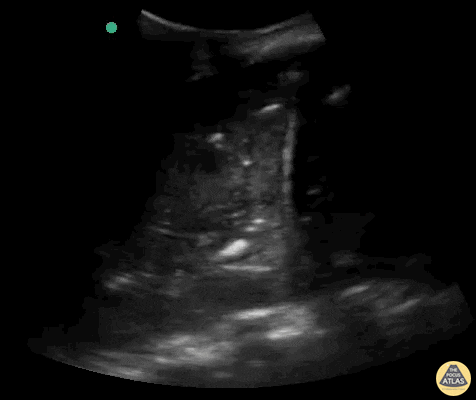

Pulmonary - Massive dynamic air bronchogram

Massive lung consolidation in a patient diagnosed with COVID-19 with bacterial component. Contributor: Rafael Intensivanaveia - Critical Care Physician at Hospital Israelita Albert Einstein